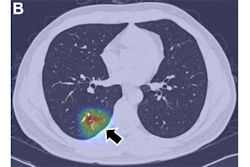

Lung adenocarcinoma is the most common primary lung cancer seen in the U.S. Tumors manifest as ground-glass nodules (GGNs) on CT scans. Deciding whether the lesions are preinvasive, minimally invasive, or invasive, however, is a significant challenge, and these determinations drive the timing of surgery, according to the authors.

To address this challenge, the group developed their deep-learning and radiomics-based approach, which classifies GGNs into preinvasive (atypical adenomatous hyperplasia or adenocarcinoma in situ), minimally invasive, or invasive adenocarcinoma.

In brief, the researchers first constructed three conventional ternary classification models: model 1 was constructed by using a radiomics method; model 2, by a deep-learning method; and model 3, by a joint learning method combining both radiomics and deep learning. The models were progressively modified through framework optimization, joint learning, and an “adjudication strategy,” the authors wrote.